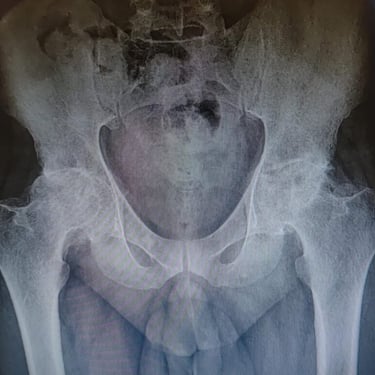

Hip replacement surgery and revision surgery

Gallery